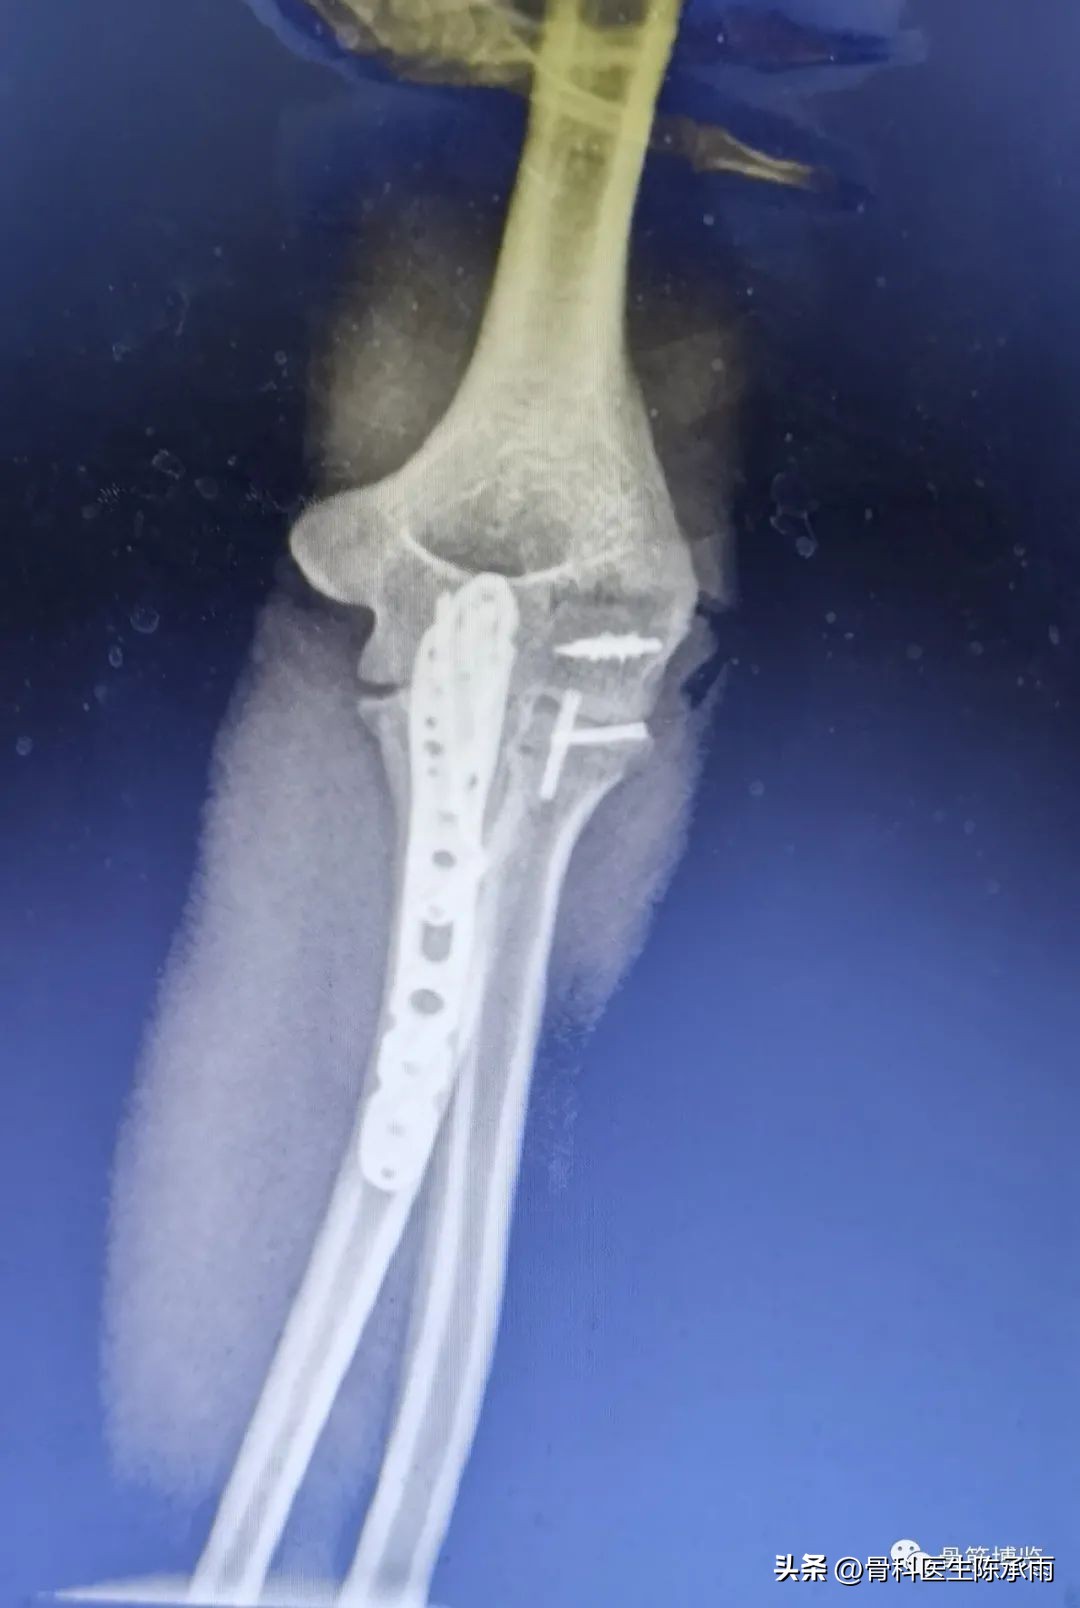

这是最近的1例手术,合并了尺骨鹰嘴骨折,采用后侧入路

术后复查